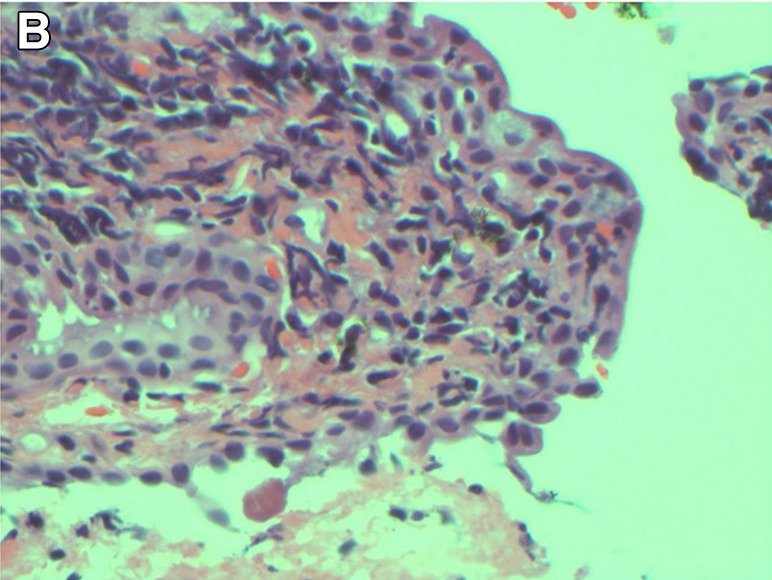

Η Τερέζα και η Δρ Ντάνα Ρόμπεϊ έδωσαν στη δημοσιότητα τις φρικτές εικόνες για να δείξουν τους κινδύνους του να μην αφαιρείται τη μάσκαρα το βράδυ πριν πέσετε για ύπνο.

Η Δρ. Ρόμπεϊ, που δημοσίευσε μια μελέτη για την περίπτωση της Τερέζα, είπε πως δεν είχε ξαναδεί και παρόμοιο και πως κινδύνευε να μείνει τυφλή και πρόσθεσε πως ελπίζει ότι η περίπτωση αυτή θα είναι μια σημαντική πλατφόρμα για την ευαισθητοποίηση σχετικά με τους κρυφούς κινδύνους των καθημερινών προϊόντων ομορφιάς.

Όπως είπε η γιατρός: «Κάθε φορά που η Τερέζα ανοιγόκλεινε τα μάτια της, αυτοί οι θρόμβοι έτριβαν την επιφάνεια του ματιού και έθεταν σε κίνδυνο την όρασή της. Εάν η γρατσουνιά στην επιφάνεια του ματιού μολυνόταν, υπήρχε ο κίνδυνος να τυφλωθεί, αν και ήταν σπάνιο».